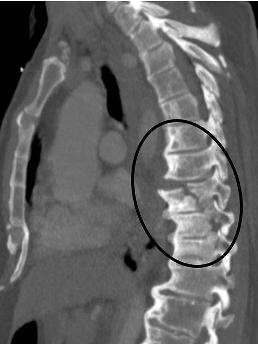

胸12椎体骨折屈曲牵张型损伤

图片尺寸1198x1598